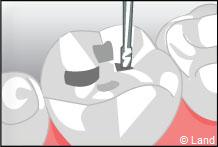

Il est composé de 3/4 de charges inorganiques et 1/4 de résine de synthèse.

Il est réalisé en une séance. Il imite parfaitement la dent.